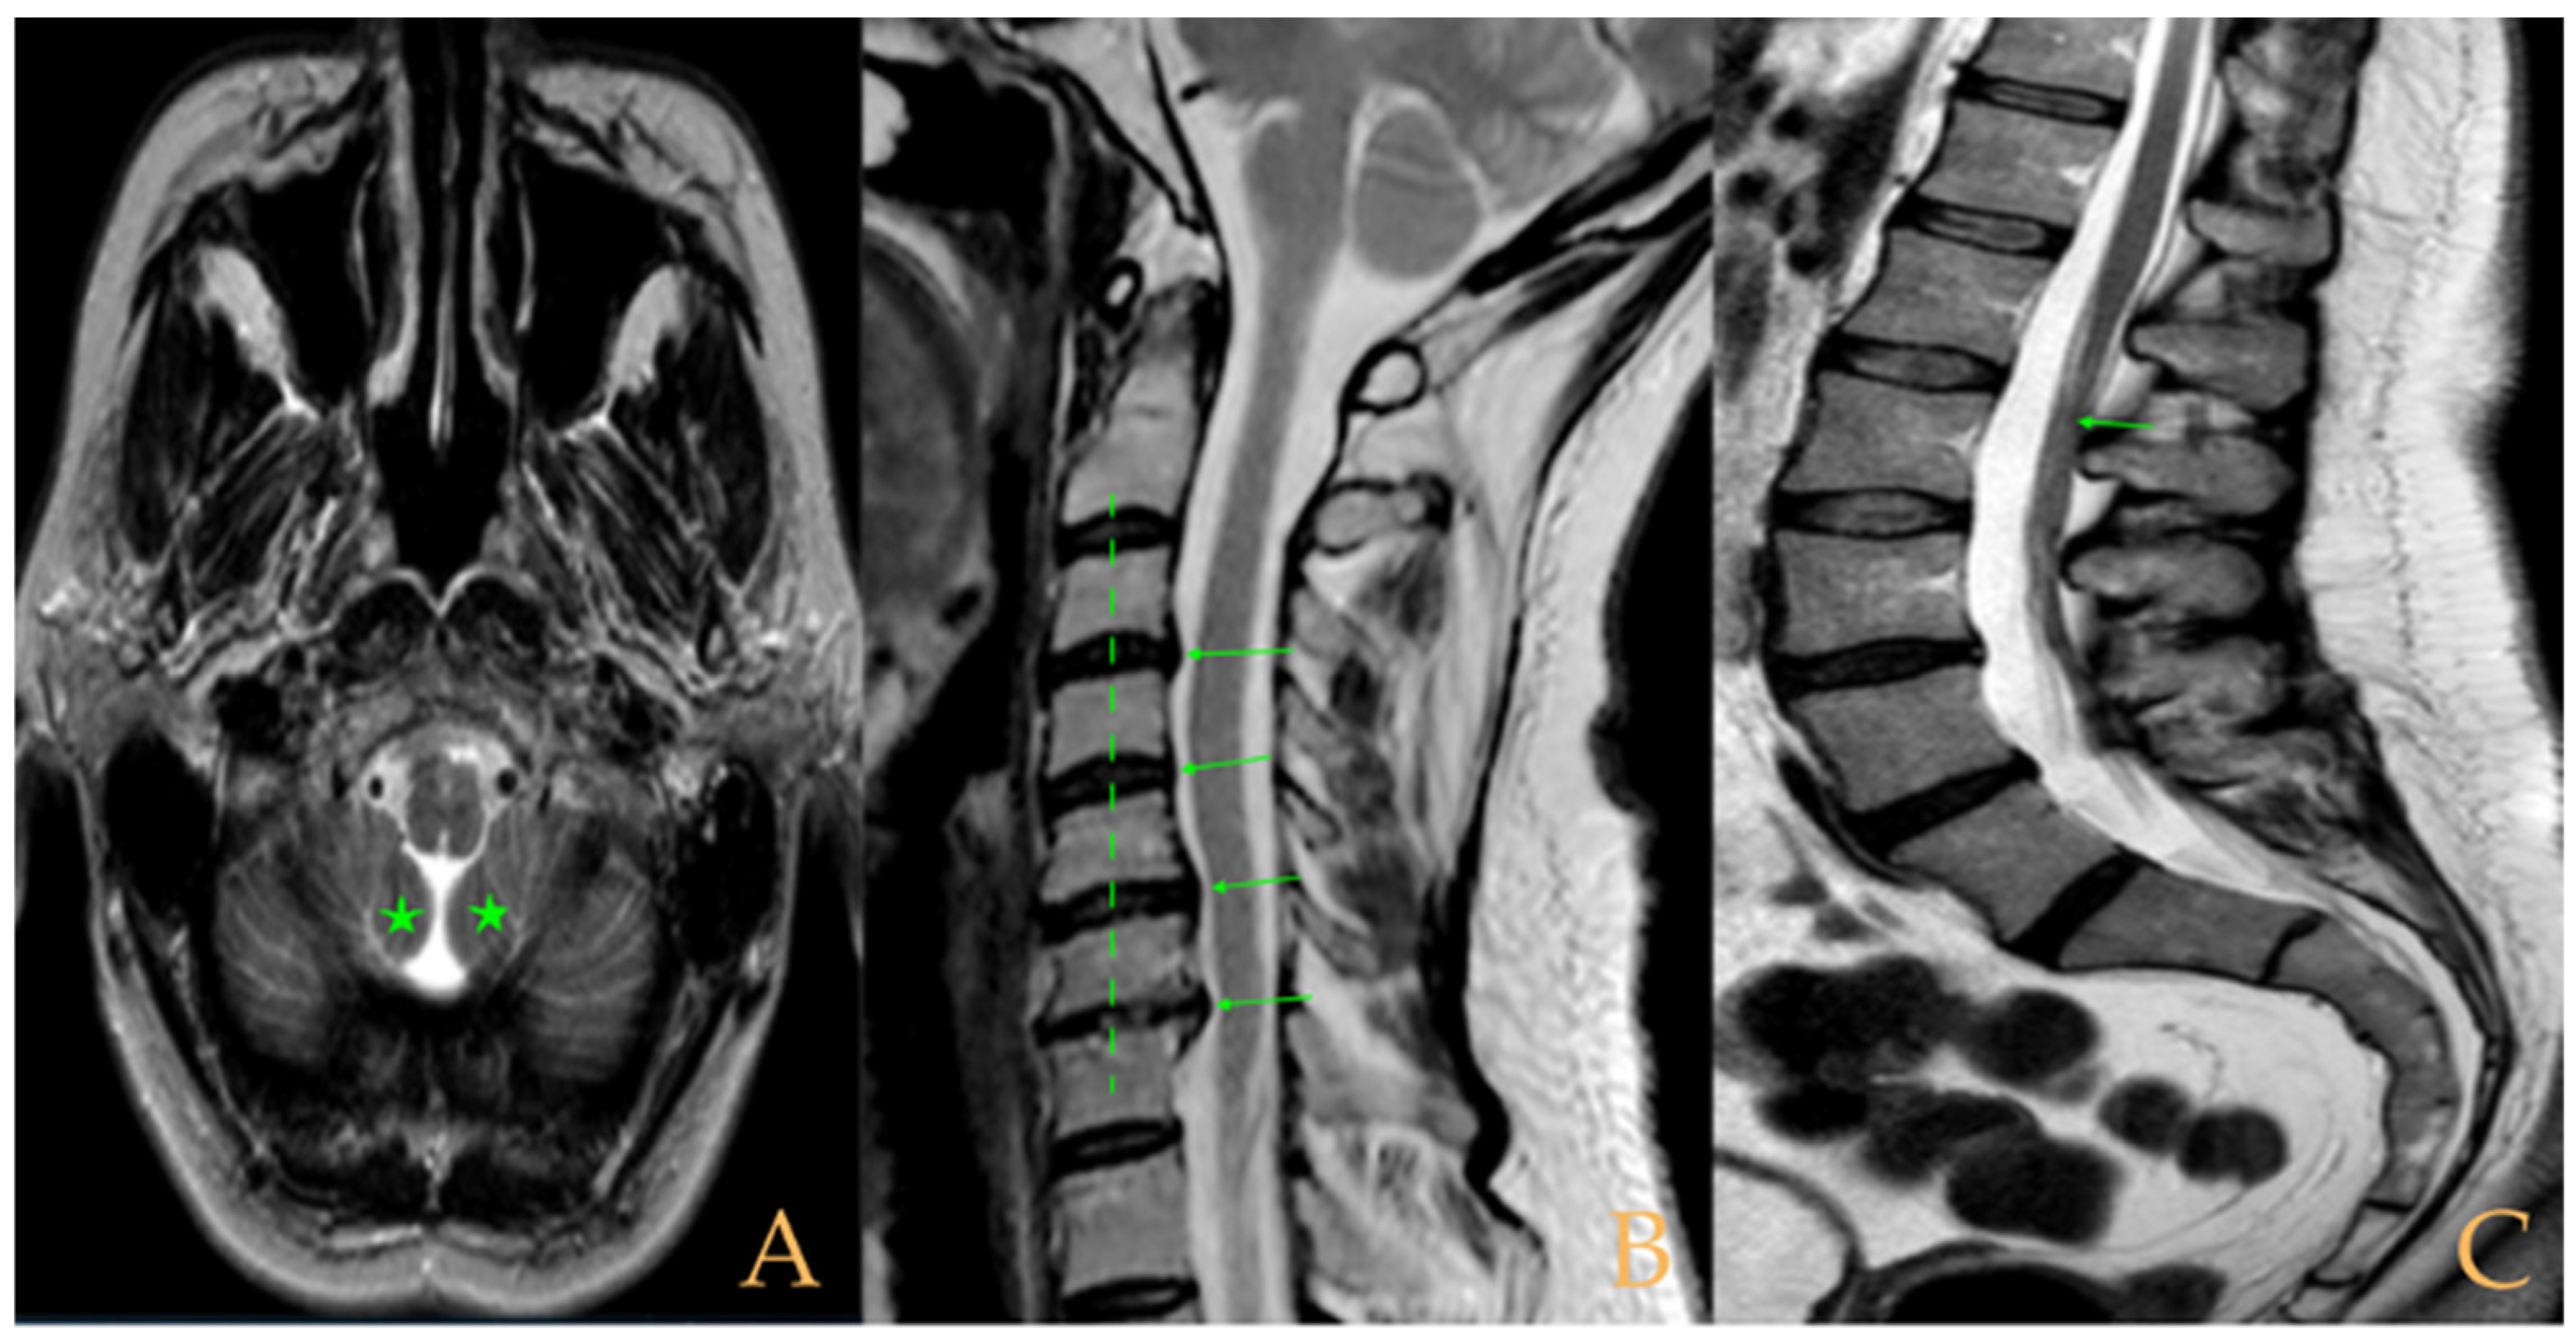

The MRI showed a descent of the cerebellar tonsils, increased supracerebral space, and micro lacunae in the bilateral white matter and the left basal ganglia. Upper cervical kyphosis and straightening in the lower levels. Surgical arthrodesis at C4-C5 and C5-C6. Cervical, thoracic and lumbar protrusions. Ischemia and oedema in the cervical and thoracic spinal cord. Slight cervical rotoscoliosis. Disc protrusions: T7-8, T11-L1, L2-L3-L4, and disc herniation L4-L5. Loss of the lumbar lordosis. Conus medullaris at the level of the middle third of the L1 vertebra (Figure 2). The X-ray images of the entire spine showed levoconvex thoracolumbar scoliosis of 21°, dysmetria of the lower extremities with shortening of the right lower extremity by 10 mm, with respect to the level of the hip, and 99 mm at the level of the iliac crests, 16° cervical lordosis, 49° thoracic kyphosis, and 59° lumbar lordosis.

The cranio-vertebral magnetic resonance showed empty sella turcica, discrete descent of the cerebellar tonsils, C4-C5-C6 disc protrusions and cervical hypermobility with a tense medullary aspect in flexion in the incorporated dynamic test, and conus medullaris at the height of the TH12-L1 disc (Figure 3). No scoliosis was observed in the full-spine X-rays. The patient was not operated on. Cases 8 and 9 were very similar and involved previously diagnosed cranio-cervical and atlantoaxial instability. The patient used a cervical collar, as she was afraid that she might suffer spontaneous cervical luxation.

Figure 2. Imaging of patient 2. A: Image suggestive of spinal cord ischemia (arrows), impaction of the cerebellar tonsils (star), and straightening of the cervical spine (interrupted line); B: straightening of the upper part of the lumbar spine (interrupted line) and conus medullaris at the level of the L2L3 disc space (arrow); and C: brain MRI with micro lacunae in the white matter (arrows).

Figure 3. Imaging of patient 3. A: Empty sella turcica (arrow); B: discrete descent of the cerebellar tonsils (arrow); C: C4C5 and C5C6 disc protrusions (arrows); and D: tense spinal cord in cervical flexion (interrupted line).